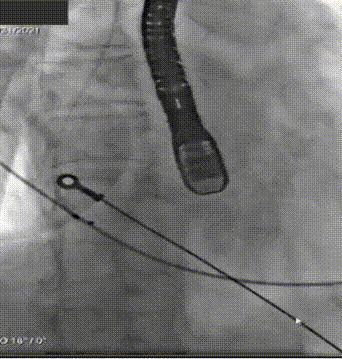

5. 根据术前评估及球囊预扩情况,选择沛嘉TaurusElite AV26号瓣膜进行植入,在120次/分快速起搏下释放瓣膜,第一次释放至工作位发生下滑;

6. 回收后进行重新定位释放,释放完毕后超声评估示平均跨瓣压差15mmHg,超声、造影评估示中量瓣周漏、少量瓣中漏,瓣膜整体下滑明显,遂行瓣中瓣策略;

7. 选择沛嘉TaurusElite AV26号瓣膜执行瓣中瓣策略,第二个瓣膜释放后造影示瓣周漏改善不明显,遂选用TaurusAtlas 22mm 球囊行后扩张;

8. 扩张后跨瓣压差降至8mmHg,造影示轻微瓣周漏,患者血流动力学指标改善明显,手术圆满成功。